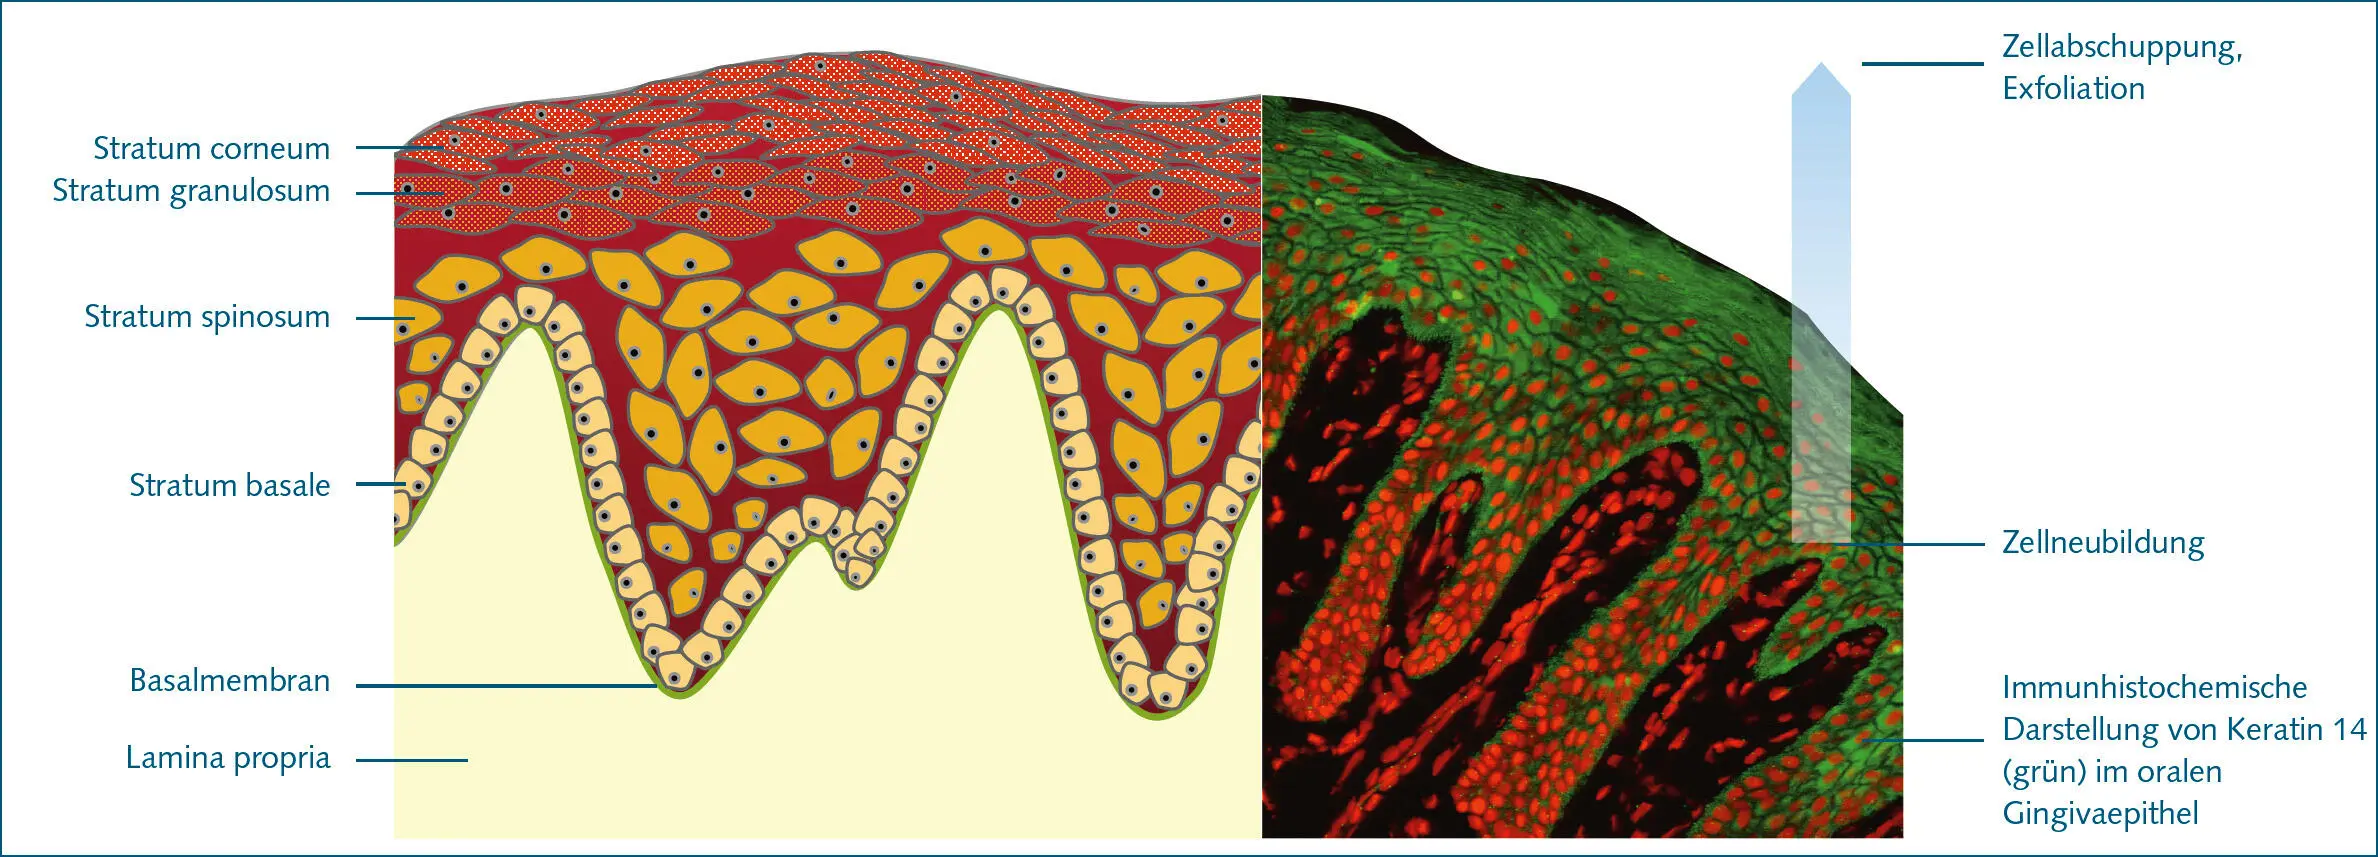

Die Gingiva wird koronal durch den Gingivasaum (Limbus gingivae) und apikal durch verschiedene Abschnitte der Mundschleimhaut begrenzt. Vestibulär geht die Gingiva an der mukogingivalen Grenze(Linea girlandiformis) in die Alveolarmukosa über. Lingual besteht eine ähnliche Begrenzung zwischen Gingiva und Mundbodenschleimhaut. Palatinal geht die Gingiva ohne Begrenzung in die Schleimhaut des harten Gaumens über. Die Gingiva besteht aus epithelialen und bindegewebigen Anteilen (Lamina propria), sowie Nerven und Gefäßen. Die Lamina propria ist ein faserreiches Gewebe, dabei dominieren kollagene Fibrillen, die sich zu Faserbündeln gruppieren. Dabei kann man histologisch zwei Schichten im gingivalen Bindegewebe unterscheiden, das zwischen den Retezapfen des Epithels befindliche Stratum papillare sowie dem Stratum reticulare, das zwischen Stratum papillare und dem Periost des Alveolarknochens liegt. Die Gingiva besteht ferner aus zwei sich in Struktur und Funktion unterscheidenden Epitheltypen: dem Saumepithel und dem oralen Sulkus- sowie Gingivaepithel. Bei dem oralen Sulkus- bzw. Gingivaepithelhandelt es sich um ein 0,2 bis 0,3 mm dickes mehrschichtiges zumeist para- bzw. keratinisiertes Plattenepithel, das über Retezapfen mit dem Stratum papillare der Lamina propria verzahnt ist ( Abb. 3). Dieses Epithel ist widerstandsfähig gegen mechanische Belastungen und relativ undurchlässig für Bakterien und deren Produkte 1. Das orale Sulkusepithel bildet die gingivale Begrenzung des Sulcus gingivae, dem koronalen Abschnitt der dentogingivalen Berührungsfläche, in dem kein epitheliales Attachment besteht. Der Sulcus gingivae hat einen V-förmigen Querschnitt und gestattet das ungehinderte Eindringen einer Parodontalsonde. Unter idealen Bedingungen, die nur experimentell bei keimfreien Versuchstieren oder nach einer Phase intensivster Plaquekontrolle dargestellt werden können, ist die koronoapikale Ausdehnung des Sulcus gingivae 0 oder nahe 0 mm. Unter klinisch normalen Verhältnissen beim Menschen findet man mittlere Sulkustiefen von etwa 2 mm.

Abb. 3 Das orale Gingivaepithel bedeckt die vestibulären und oralen Oberflächen der marginalen Gingiva und besteht aus vier Schichten: Stratum basale (Basalzellschicht), Stratum spinosum (Stachelzellschicht), Stratum granulosum (Körnerzellschicht) und Stratum corneum (Hornschicht).